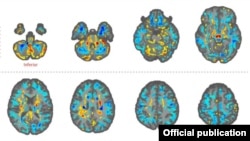

Las imágenes revelaron “diferencias significativas en el volumen de materia blanca cerebral total, [en] volúmenes locales de materia blanca y gris”, y en la integridad microestructural del tejido del cerebelo. También mostraron diferencias de “conectividad en las subredes auditivas y visoespaciales, pero no en la subred de control ejecutivo”.

En declaraciones al periódico británico The Guardian, Verma observa que los resultados de la investigación son desconcertantes, porque los cerebros de los diplomáticos mostraron lo contrario de lo que comúnmente aparece cuando hay daño cerebral.

En vez de dilatarse, la región llamada vermis –que ayuda a coordinar los movimientos del tronco y de las extremidades y maneja señales visuales y auditivas-- se contrajo, y lejos de disminuir, un factor de análisis clínico llamado anisotropía fraccional aumentó.